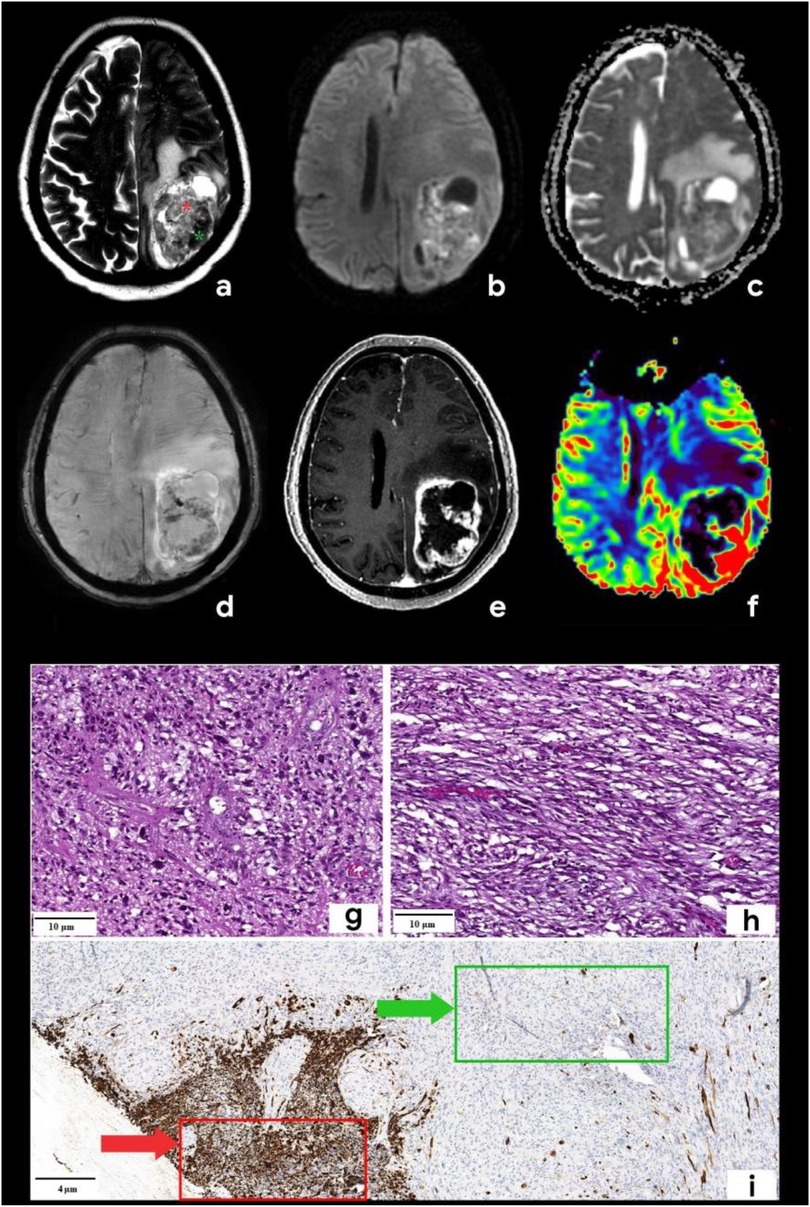

A 55-year-old man was admitted to Regional Hospital №2 (Tyumen, Russia) after he experienced a transient loss of consciousness. He presented with complaints of right-sided limb weakness and disorientation for 12 h. Upon admission to the hospital, a computed tomography (CT) scan of the brain without contrast administration was performed using a General Electric Revolution Evo CT scanner (GE Healthcare, USA, Chicago, IL). Axial images were acquired with 0.625 mm slice thickness and reformatted by multiplanar reconstruction (MPR). CT imaging revealed an intra-axial heterogeneous mass in the left frontoparietal region associated with the mass effect, resulting in a brain midline shift. Based on the mpMRI protocol, a specialized radiological examination was performed. A magnetic resonance imaging of the brain was performed using a 1.5-T General Electric Signa Voyager MRI scanner (General Electric HealthCare, China). The mpMRI protocol includes conventional sequences such as T1-weighted imaging (T1WI), T2-weighted imaging (T2WI), T2-FLAIR, and diffusion-weighted imaging (DWI) with apparent diffusion coefficient (ADC) maps. Specialized MRI sequences include sequences sensitive to compounds that distort the local magnetic field [e.g., SWI, susceptibility-weighted imaging (SWAN), T2*] and dynamic susceptibility contrast (DSC) T2-weighted perfusion. Images were acquired in three orthogonal planes (axial, sagittal, and coronal) with a slice thickness of 1–5 mm, both before and after gadolinium-based contrast agent administration. A multiparametric MRI revealed a cystic-solid mass in the left frontoparietal region closely adherent to the dura mater. The lesion was surrounded by a marked area of vasogenic edema and had a severe mass effect. On postcontrast T1-weighted imaging, the tumor exhibited a ring-like enhancement and a vascular network with intratumoral hemorrhages on the SWAN. Perfusion maps demonstrated elevated relative cerebral blood volume (rСBV) within the tumor exceeding normal values of unaffected white matter by three to five times (11). A detailed analysis of the T2-weighted sequence (Figure 1a) revealed signals of heterogeneity within the solid component of the tumor, composed of two distinct regions: a hypointense area (green star) and a hyperintense area (red star).

Figure 1. Brain mpMRI and pathology of the patient with gliosarcoma. MRI: (a) Т2, (b) DWI, (c) ADC, (d) SWAN, (e) T1 + C, and (f) CBV. There is a mass with a perifocal edema located in the left frontoparietal area. On T2WI (a), the tumor is characterized by signal heterogeneity: a hypointense one (green star) and a hyperintense component (red star). The tumor has a ring-like rim contrast enhancement (e), the diffusion restriction of the solid part (b,c) with corresponding zones of high CBV (f). SWAN (d) shows the presence of vascular shunts within the tumor. Pathology: staining scale bar: 4 and 10 µm, hematoxylin and eosin staining (g,h) and acidic protein (GFAP), immunohistochemistry (i). (g) and (h) are histopathological signs of classic glioblastoma: the glial part demonstrates the marked nuclear polymorphism and the cellular atypia (g), sarcomatous part (h) is presented by the spindle-shaped cells with argyrophilic fibers (mesenchymal tissue). I–GFAP demonstrates the marked expression in the glial part of the tumor (red arrow) and the total absence of the expression in the sarcomatous one (green arrow).

Based on the tumor's location and contrast enhancement pattern, the differential diagnosis mainly included solitary metastasis or malignant diffuse glioma but also considered the possibility of anaplastic meningioma. Because of the midline shift syndrome and progressive neurological deterioration posing a life-threatening risk, a microsurgical resection of the mass was performed. The surgical specimen was submitted for a pathomorphological examination. A microscopic analysis identified a rare variant of gliosarcoma characterized by a biphasic pattern: a glial component (Figure 1g) exhibiting marked nuclear polymorphism, cellular atypia, and hyperchromatic nuclei and a sarcomatous component (Figure 1h) composed of spindle-shaped cells arranged in fascicles and interspersed with argyrophilic fibers. An immunohistochemical analysis of the glial fibrillary acidic protein (GFAP) revealed a strong positive expression in the glial component of the tumor (indicated by a red arrow in Figure 1i) and a complete absence of expression in the sarcomatous component (marked by a green arrow in Figure 1i). The patient was discharged in satisfactory condition on the 15th postoperative day and referred to a neuro-oncologist at the Multidisciplinary Clinical Medical Center “Medical city” to determine further treatment strategies and initiate chemoradiotherapy. The diagnostic process of the patient is illustrated in Figure 2.